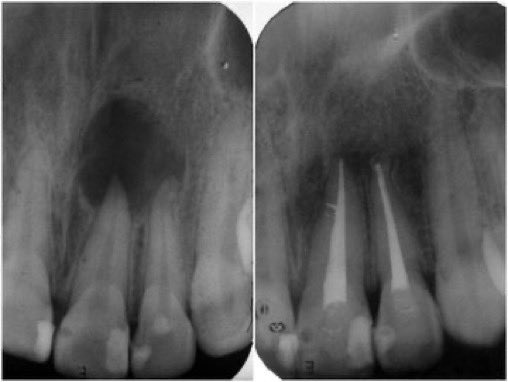

التهاب العصب السني: (٥)

هذه الخراجات 7️⃣ يمكن التخلص منها بإذن الله بعمل علاج للجذور وتعقيمها (بوجود العازل المطاطي✅) وعمل الحشوات النهائية ومتابعة تقلص الخراج من خلال الاشعة الدورية.